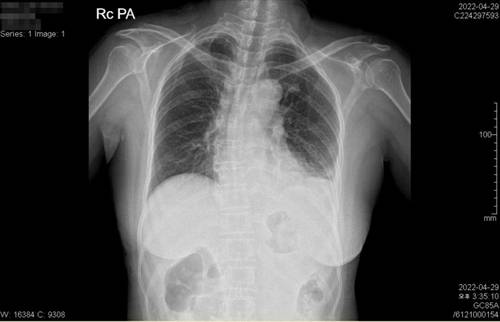

B씨는 "어머니가 ESD 시술 후 단순 통증(쓰림)이 아닌 다른 양상의 극심한 통증을 호소했음에도 병원은 마약성 진통제를 투여하고 엑스레이만 찍은 후 위 천공을 의심하지 않았다. 또 엑스레이에는 왼쪽 폐에 물이 차는 무기폐가 나타났고 어머니가 호흡곤란을 호소했음에도 방치했다. 천공으로 인한 복막염과 패혈증이 원인이었던 무기폐만 확인하고 문제를 해결하려 했다면 상태가 크게 악화하지 않았을 것"이라고 주장했다.

![엑스레이에 나타난 무기폐 A씨의 왼쪽 폐에 하얀 부분이 물이 찬 무기폐의 모습이다. 무기폐는 위 천공 후 복막염과 다발성 장기부전, 패혈증 때문에 발생한 것으로 추정되지만 병원은 조기에 치료하지 않았다. [A씨 아들 B씨 제공]](https://img2.daumcdn.net/thumb/R658x0.q70/?fname=https://t1.daumcdn.net/news/202307/01/yonhap/20230701070009471rqxh.jpg)